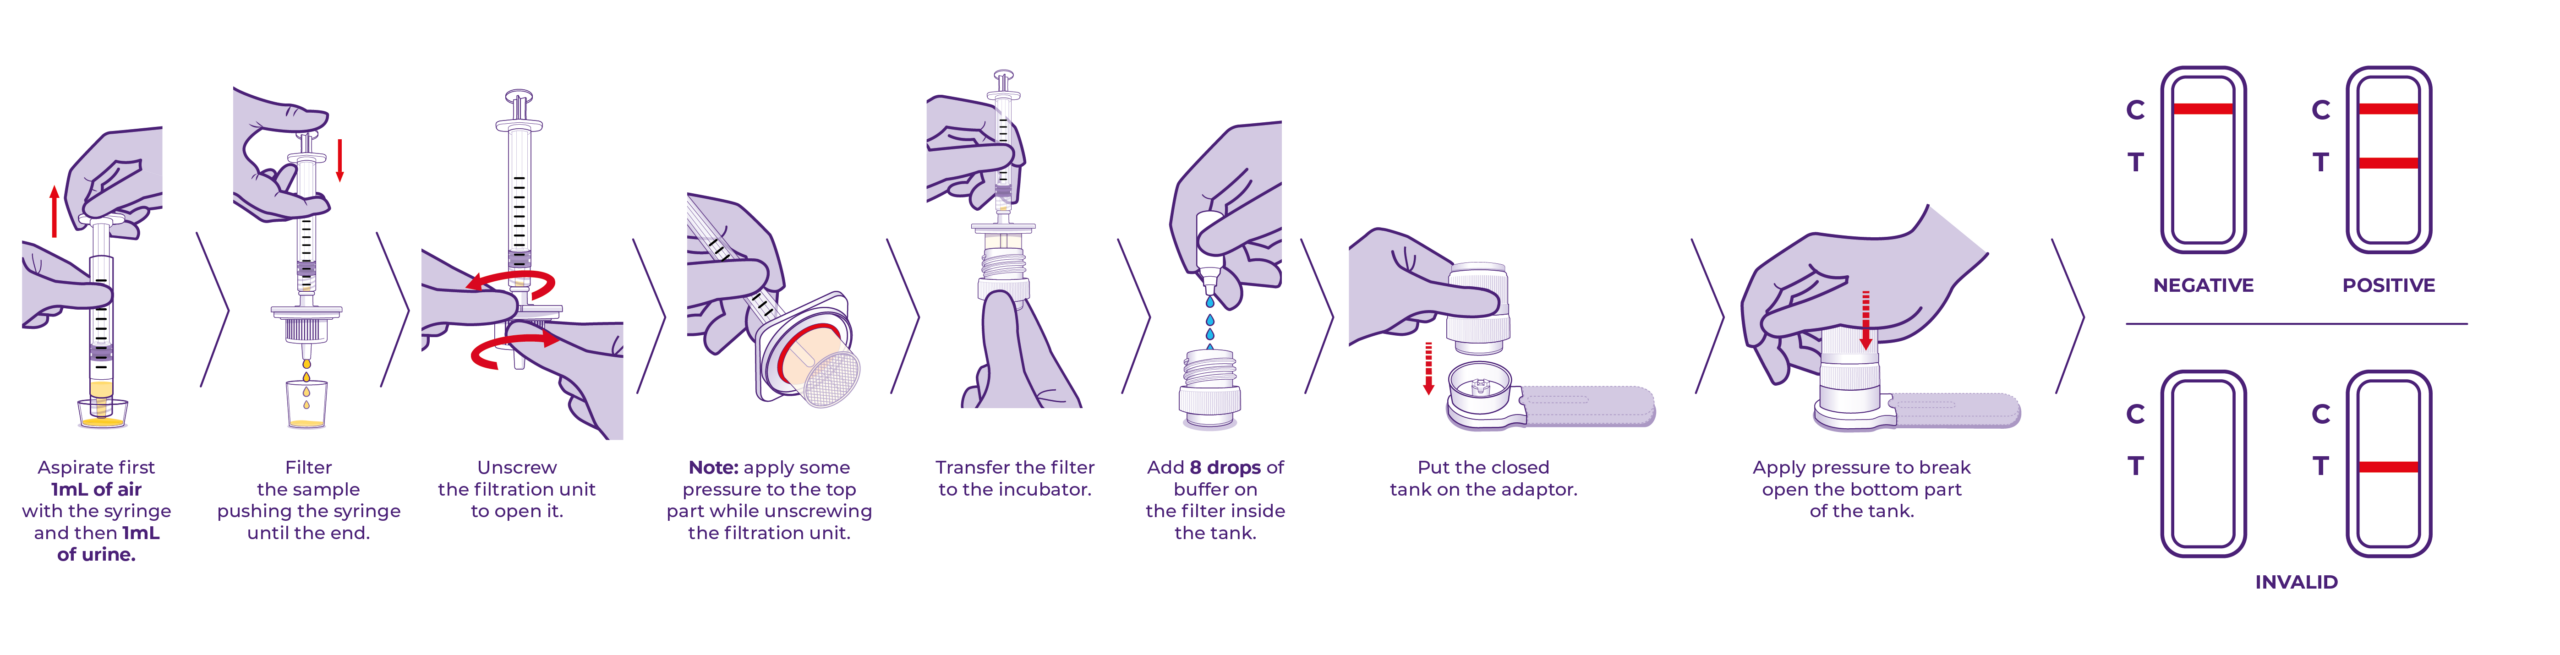

NG-TEST® Vet Direct CRE

NG-TEST® Vet Direct CRE NG-TEST® Vet test are easy-to-use and allows to have results in 15 min bacteria sample without any instrument.

NG-TEST® Vet Direct CRE is a ready-to-use kit comprising a sample preparation device (DirecTool) and a rapid test in cassette format (CARBA-5) designed for the detection and differenciation of the five most common carbapenemase families.

PRINCIPLE

The NG-TEST® Vet Direct CRE is a rapid multiplex immunoassay for the detection of one or more of the five common types of carbapenemase enzymes (KPC (K), OXA-48-like (O), IMP (I), VIM (V), NDM (N) in Enterobacterales and Pseudomonas aeruginosa extracted directly from urine sample.